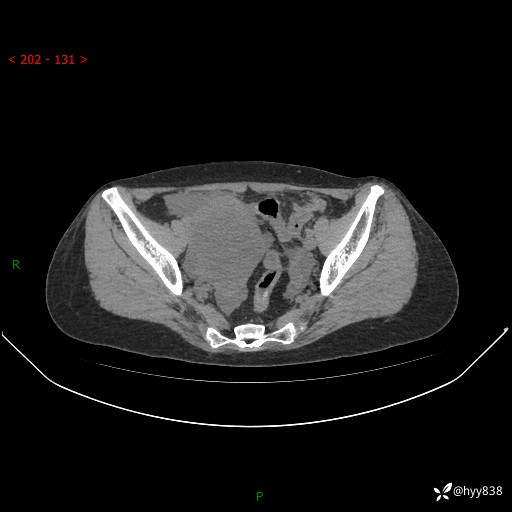

腹盆CT平扫

增强